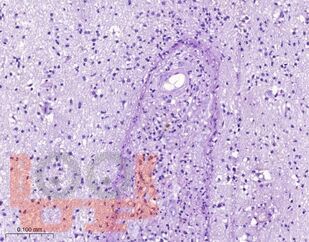

Церебральный токсоплазмоз

Учебное пособие посвящено актуальным вопросам патогенеза, клинического течения, диагностики и лечения церебрального токсоплазмоза у ВИЧ-инфицированных пациентов. Особое внимание уделено вопросам дифференциальной диагностики церебрального токсоплазмоза от другой патологии нервной системы, в том числе опухолей головного мозга, нарушений мозгового кровообращения, воспалительных заболеваний. В пособии представлены собственные клинические наблюдения многоочаговых и солитарных форм церебрального токсоплазмоза.